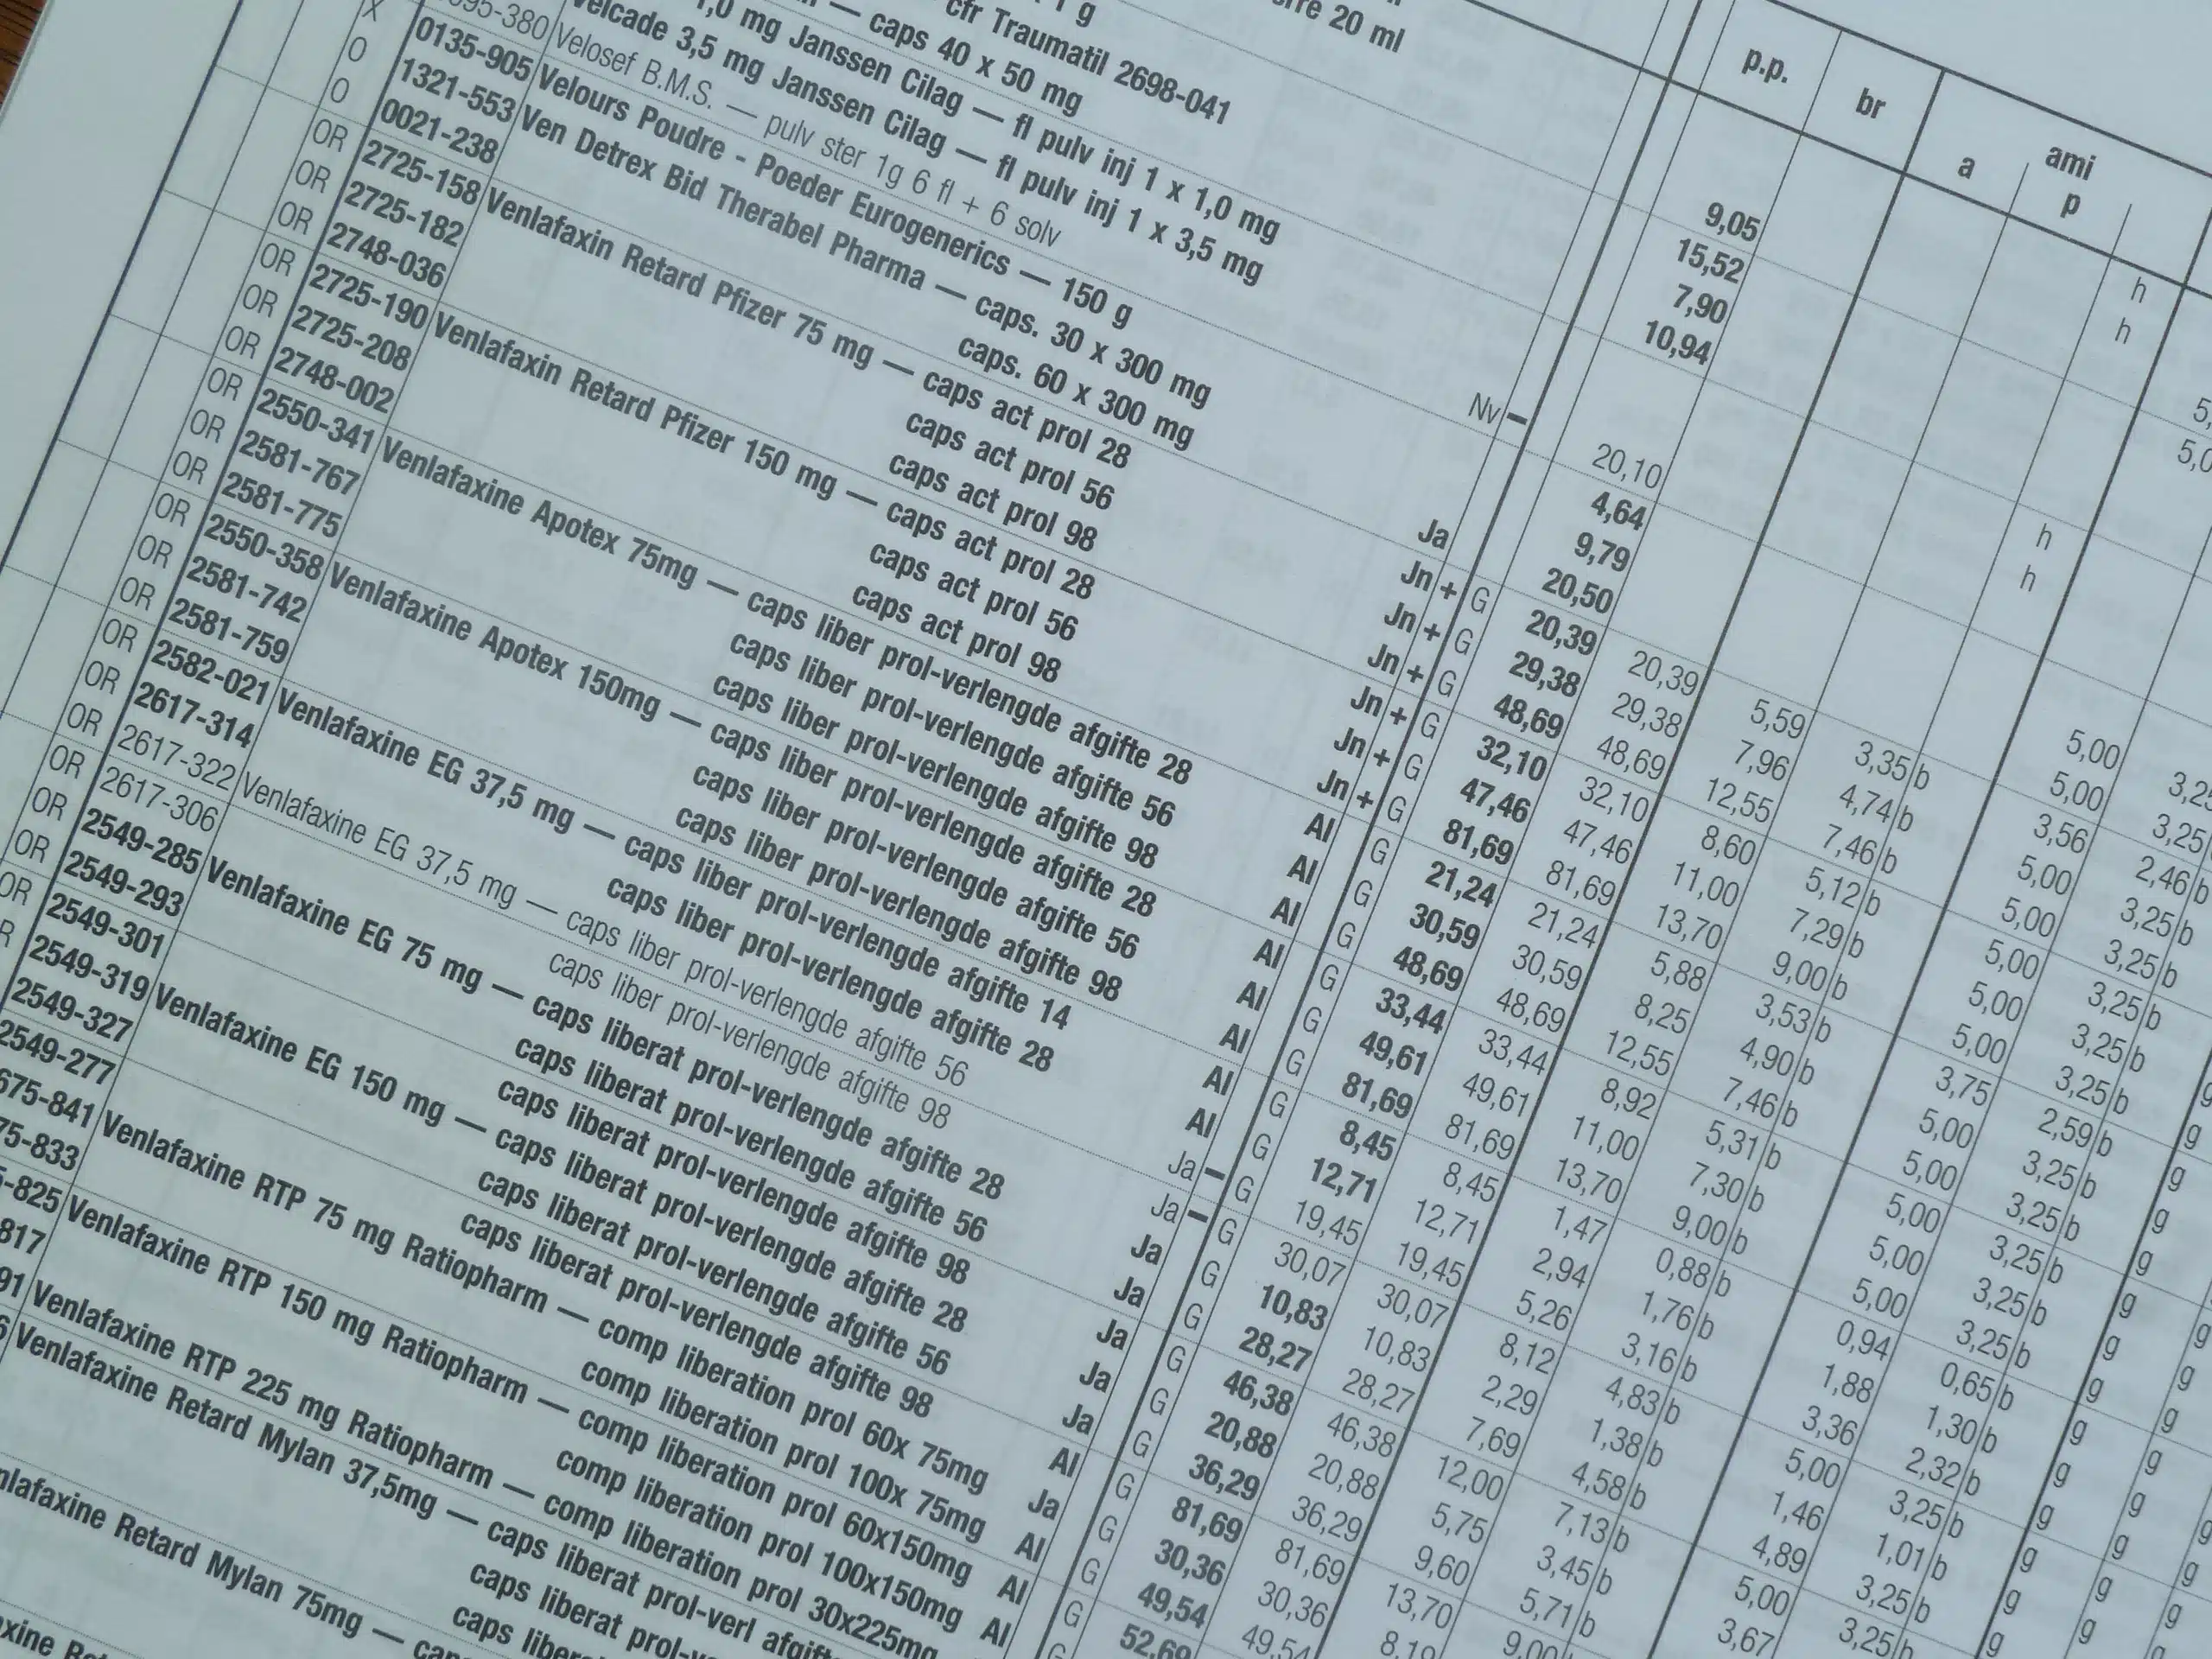

MODIFICATIONS DE PRIX ET REMBOURSEMENT AU 1ER OCTOBRE 2022

1. Baisses de prix au 1er octobre 2022: cliquez ICI Source APB 21/09/2022 2. Listes officieuses des spécialités les « moins chères » : à consulter sur le site APB Voir la page du site APB: cliquez ICI 3. Modifications des modalités de remboursement de spécialités au 1er…